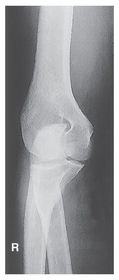

AP Elbow Fully Extended 60-75 kV 40 SID 14x17 IR nongrid CR @ mid-elbow joint MUST SEE entire elbow joint very slight superimposition of radial head by the ulna

Epicondyles must be _____ to the IR for an AP fully extended elbow projection. Parallel